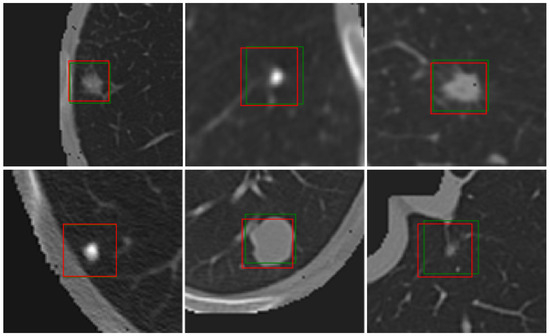

- The first contribution of this study is the integration of a dual-attention mechanism into the final layers of the OMS-CNN. The dual-attention mechanism enhances the network’s ability to capture both spatial and channel-wise dependencies within the feature maps. By incorporating both spatial attention, which emphasizes important regions in the image, and channel attention, which focuses on relevant feature channels, the DA OMS-CNN achieves improved sensitivity in detecting small lung nodules. This approach ensures that critical regions and fine-grained details in the input data are highlighted, leading to more accurate and robust feature extraction.

- The second contribution is the introduction of the dual-attention RoIPooling (DA-RoIPooling) mechanism at the classification stage of the framework. DA-RoIPooling applies spatial and channel-wise attention to the pooled features, enabling the model to focus on the most relevant features within each region of interest (RoI). This dual-attention mechanism ensures that the classification network emphasizes the key characteristics of the nodules while suppressing irrelevant background information. By refining the feature representation within the RoIs, DA-RoIPooling improves the overall classification accuracy, particularly in distinguishing true nodules from false positives. This innovation significantly enhances the performance of the Faster R-CNN framework by reducing misclassifications and improving sensitivity and precision, particularly for challenging cases.

3.3. Lung Nodule Detection

3.3.1. Dual-Attention Optimized Multi-Scale CNN (DA OMS-CNN)